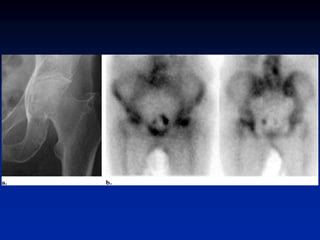

Legg-Calve-Perthes • early imagingphoton deficient lesion • increased activity with healing (for months)

• 58.